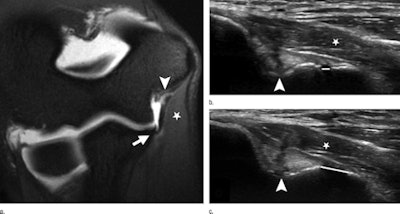

With stress ultrasound, players' elbows were flexed at approximately 30° and held in that position by one of Thomas Jefferson's resident physicians. For rest ultrasound, the elbow remained at that angle without valgus stress and the width -- or gap -- of the ulnotrochlear joint space at the UCL was measured on the ultrasound screen. Increased joint gapping indicates a tear of the UCL.

"The ligament essentially provides stability. If it tears or is injured, you can 'gap open' the joint when there is stress on [the UCL]," Roedl explained. "We wanted to look at what measurement should be used? What is the threshold? What is too much of an opening that would indicate a tear?"

When they examined the images of each player's elbows, the researchers found a significant difference in the joint gap of the injured elbow (3.7 mm ± 1.3 mm) versus the joint gap of the contralateral, or uninjured, elbow (1 mm ± 0.3 mm). Using a joint gap threshold of greater than 1 mm between the injured and uninjured elbows, the combination of ultrasound and MR produced greater sensitivity, specificity, and accuracy for diagnosing UCL tears.